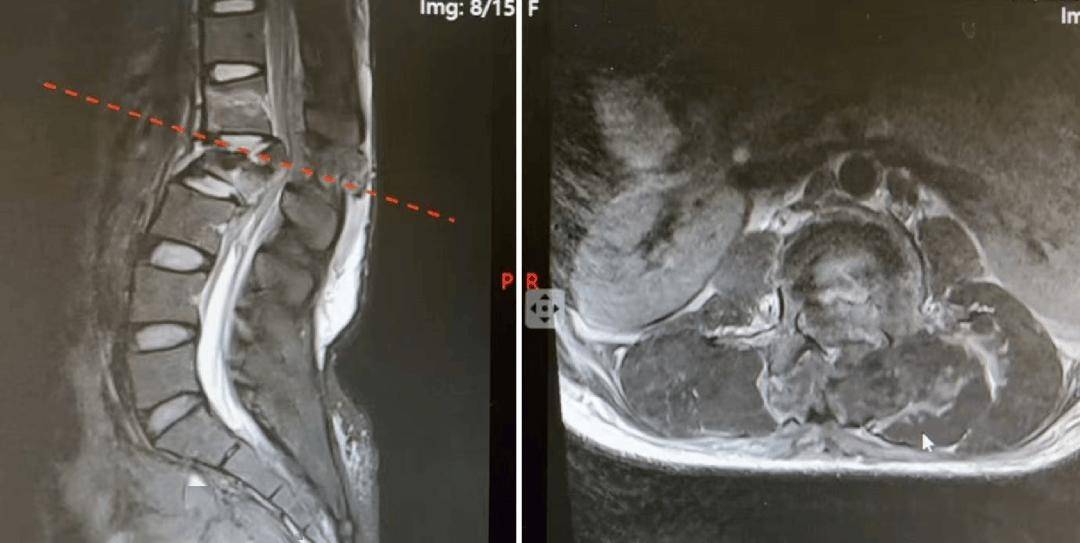

患者术前核磁共振影像

术中,骨病中心六部主任医师周立金与主治医师张苡齐团队,在保障患者生命安全的前提下,快速精准完成切开复位内固定及神经减压手术。

术后影像学复查显示,骨折复位良好,内固定位置满意,患者受损神经功能得到有效挽救。